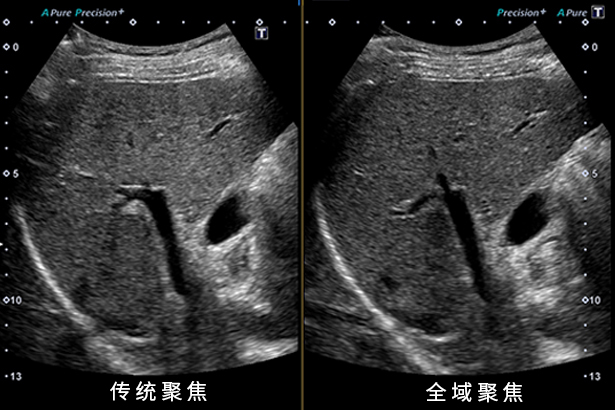

全域聚焦功能讓您從進場到遠場,在任何深度都有清晰、一致的圖像,減少按鍵操作調節聚焦點。